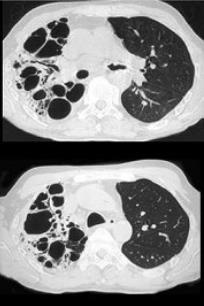

男,31岁,反复咳嗽,咯血10年余,结合影像学检查,最可能的诊断是()。

A、肺囊肿

B、间质性肺炎

C、肺曲菌病

D、支气管扩张

E、肺结核

D